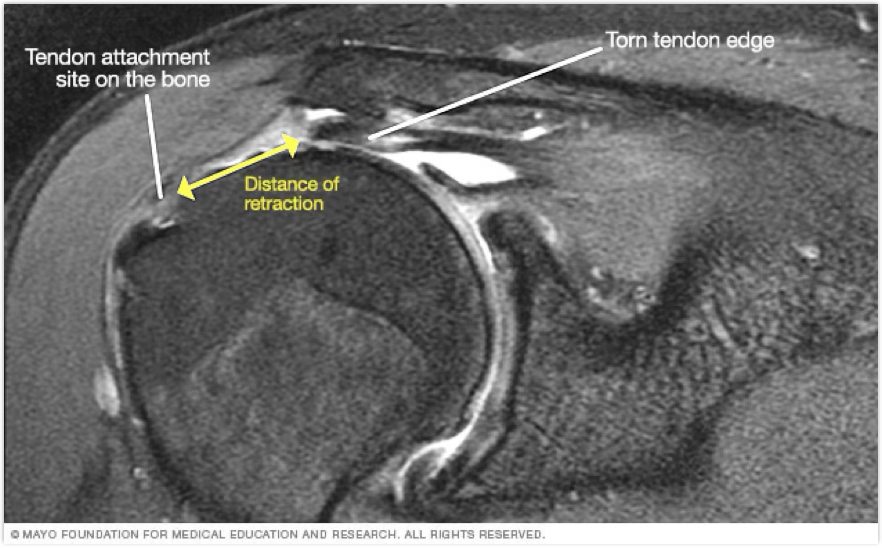

how does a rotator cuff tear occur?

tends to come at the insertion of the muscles

can be partial or full thickness tear

full thickness tends to be overhead athletes over 40 y/o with history of RC injuries

rotator cuff tear symptoms

pain and lack of IR/ER ROM

rotator cuff treatment

management depends on tear

Partial is conservative with PT

Full is surgical and immobilization